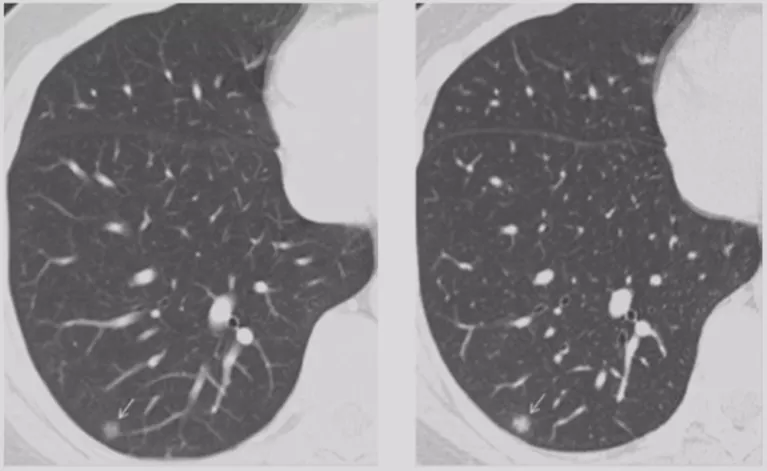

要观察大小、实性成分和形态的变化。大小的变化很有讲究,现在国际上比较推荐使用容积法(3D),需要专用软件来测量,一定要减少误差。

GGO自然变化与随访结果

基本上是这几种随访结果:第一种,结节没有变化;第二种,实性成分增多;第三种,结节消失。后两种都好处理,关键是没有变化的GGO,下一步该怎么办呢?国际上建议,GGO观察三个月,如果持续存在,结节实性成分>5mm可以手术;大小长到了1.5cm,要密切观察或者直接手术;如果稳定至少要观察三年。如果是混合性实性结节,实性成分>5mm可以手术;如果大小>15mm可以手术,针对不同的情况,都有不同的规定。